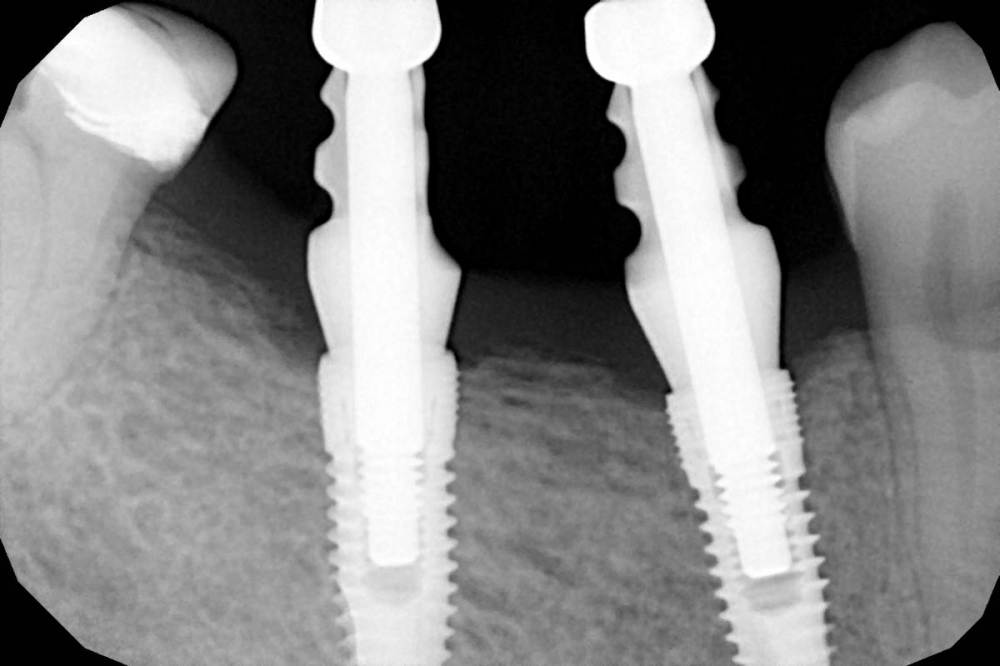

Женька Опубликовано 23 апреля, 2021 Поделиться Опубликовано 23 апреля, 2021 Коллеги здравствуйте! подскажите пожалуйста какой абатмент вы выбрали бы в данной ситуации? Планируется две мк-коронки, хочется сформировать сосочки ещё плюсом. Фиксируем сразу постоянную работу, потому, скорее всего на фиксации будем десну резать. Фото прикладываю Вторая риска на глубиномере уже видна глазом - это 2.5мм. Правильно ли я размышляю, что надо взять 1.5мм высоту субгингивальной части, чтобы профиль прорезывания получился плавный? И не будут ли эти 1.5мм от кости фатальны в долгосрочной перспективе? И где должна быть граница керамической массы? Слышал, что керамика под десной не есть хорошо, так ли это? Ссылка на комментарий

Snow Doc Опубликовано 25 апреля, 2021 Поделиться Опубликовано 25 апреля, 2021 1 минуту назад, Женька сказал: @Snow Doc 0.5 мм под десну уже хватит? или лучше от 1мм стартовать? И спасибо за ответ, док! Я бы 1мм под десну лез, особенно, если резать И посмотреть бы прицельный, хотя бы. Ссылка на комментарий

Snow Doc Опубликовано 25 апреля, 2021 Поделиться Опубликовано 25 апреля, 2021 7 минут назад, Женька сказал: А снимки вы наверное видели) из темы "Только я начал думать что стало получаться" Хотя там после этого была мягкотканная пластика и уровень десны на модели виден Надо научить асю делать прицелки перпендикулярно оси импланта. Интересны снимки с уже установленными фдм. Тут выше 1.3 или 1.5мм тибейзов брать опасно, имхо. (Только бы кость не задавить ещё)Если пойдете одиночками - сначала фиксировать на медиальный имплант, потом на дистальный. 1 Ссылка на комментарий

Женька Опубликовано 26 апреля, 2021 Автор Поделиться Опубликовано 26 апреля, 2021 16 часов назад, Snow Doc сказал: Надо научить асю делать прицелки перпендикулярно оси импланта. Интересны снимки с уже установленными фдм. Тут выше 1.3 или 1.5мм тибейзов брать опасно, имхо. (Только бы кость не задавить ещё)Если пойдете одиночками - сначала фиксировать на медиальный имплант, потом на дистальный. с фдм не нашел, зато есть с трансферами, подойдут же? Ссылка на комментарий

Snow Doc Опубликовано 26 апреля, 2021 Поделиться Опубликовано 26 апреля, 2021 11 часов назад, Женька сказал: с фдм не нашел, зато есть с трансферами, подойдут же? Да норм. Тибейзы 1.5мм брал бы тут. Только на дистальном есть небольшие риски. И стоит перейти на трансферы, для открытой ложки. Они крутые у дентиума Ссылка на комментарий